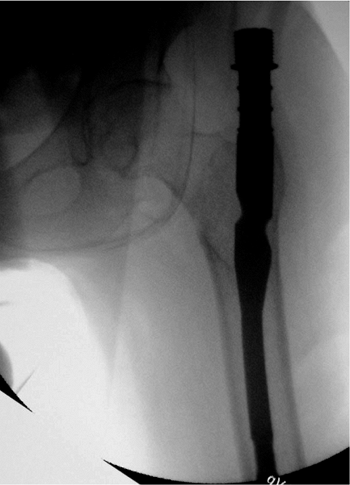

intramedullary canal. Only hand force should be required; hammering

risks iatrogenic fracture (Fig. 17.12). Usually the nail need not be inserted over a guide pin. Bi-planar fluoroscopy should be checked at this point to ensure

that the nail is not exiting the canal through the fracture and that

the nail is seated to an adequate depth. If the nail does not fully

advance but does not appear “tight” on the AP image, the surgeon should

check the lateral image to see if the tip of the nail is impinging on

the anterior cortex because most nail systems do not have a sagittal

bow to the nail. Also, soft tissue should be checked to ensure that it

is not restricting the entrance site. A combination of eccentric

entrance site reaming (primarily anterior), soft-tissue release,

isthmic (flexible) reaming, or implant downsizing will invariably solve

the problem.